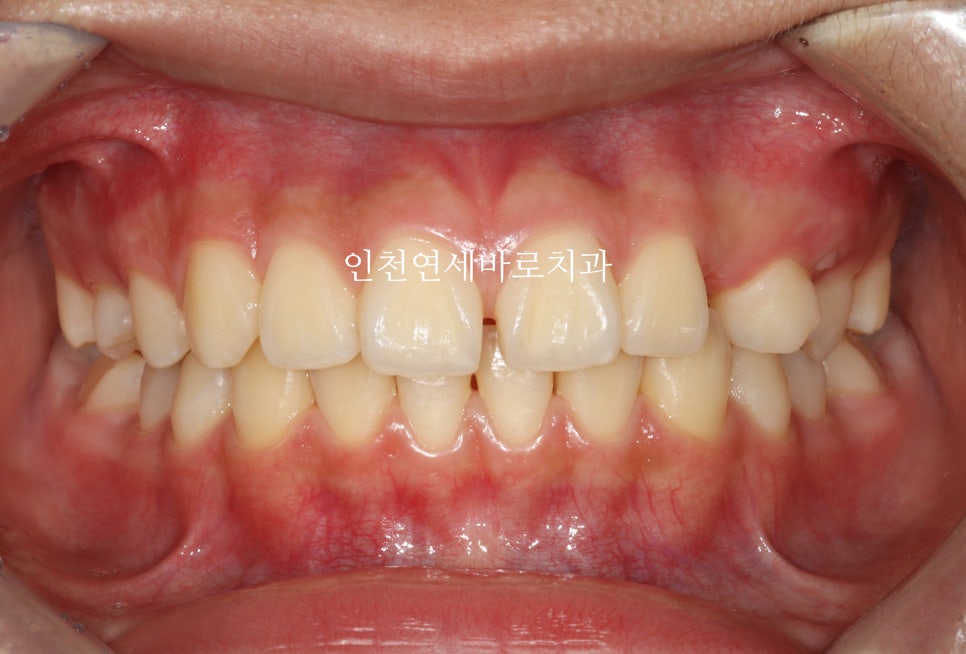

2024년 10월 – 치료 완료

총 치료기간은 10개월정도 소요되었습니다.

중심선도 잘 맞고

교합도 양호합니다.

최후방 어금니는 맹출 중 입니다.

화살표 부분의 치아 순서가 일반적인 순서와는 조금 다르지만

기능적, 심미적으로 거의 문제없이 해결했습니다.